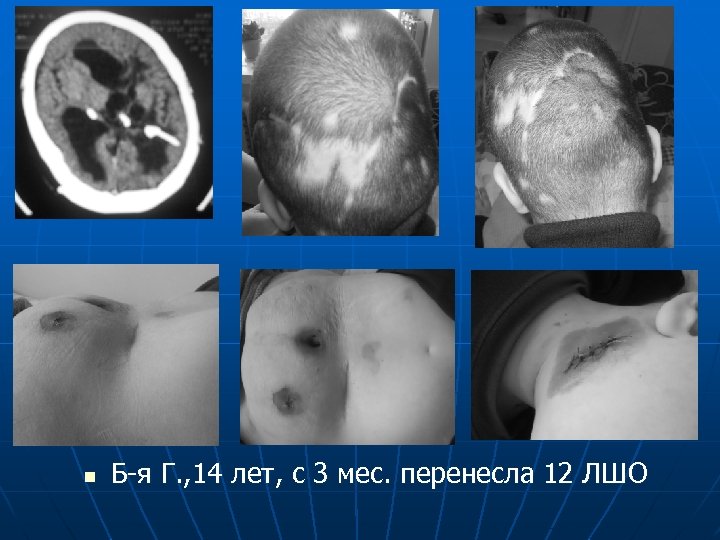

n Б-я Г. , 14 лет, с 3 мес. перенесла 12 ЛШО